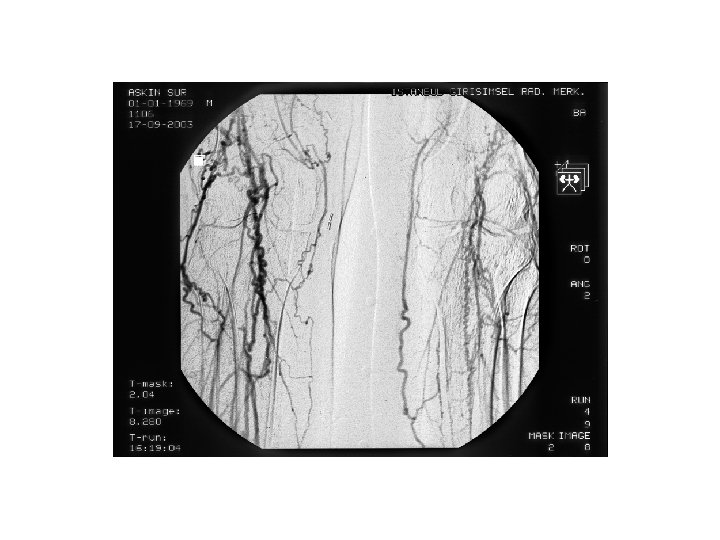

ÜST EKSTREMİTE ARTERYEL HASTALIKLARI Arteryel girişim • Arteryel girişimlerin % 5 ini oluşturur. • Subklavyen arter→Axiller arter→Brakiyel Arter→Ulnar, Radial →Palmar ark Digital arterler • Küçük , orta damarlar→Vazospasm

Adson testi • • Ateroskleroz →Subklavyen Giant cell → Subklavyen Takayasu → Subklavyen, axiller Emboli → axiller, brakiyel, el (%10 ekstremite kaybı kollateraller iyi gelişmiş) Maliniteler → tromboz Arteryel TOS (cervikal kot, 1 kot anomalileri, kallus, bandlar) → Anevrizma → emboli Subklavyen, Axiller Anevrizmaları AVF (%30 CO veya debi >1200 ml